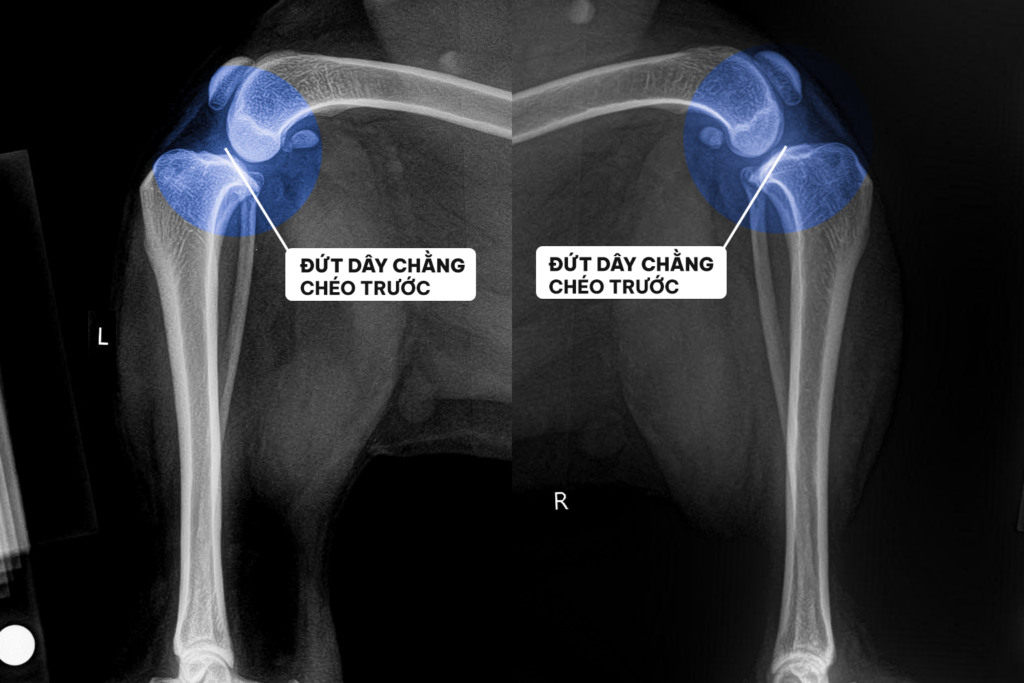

Qua thăm khám lâm sàng (Nghiệm pháp ngăn kéo trượt) và hình ảnh X-quang, bác sĩ chẩn đoán xác định: Milu bị đứt dây chằng chéo trước cả hai bên khớp gối. Khớp mất hoàn toàn sự liên kết cốt lõi, khiến mâm chày trượt tự do về phía trước, triệt tiêu động năng di chuyển và gây đau đớn dữ dội.

1. Tiếp nhận bệnh án: Mất ổn định khớp gối song phương

Bệnh súc Milu được đưa đến viện trong tình trạng mất hoàn toàn khả năng di chuyển bằng hai chân sau. Khai thác bệnh sử cho thấy, ban đầu triệu chứng đi tập tễnh chỉ xuất hiện ở một chân. Do chân đau không chịu lực, trọng lượng cơ thể dồn ép lên chân còn lại trong thời gian dài đã dẫn đến tình trạng quá tải và đứt nốt dây chằng bên chân lành.